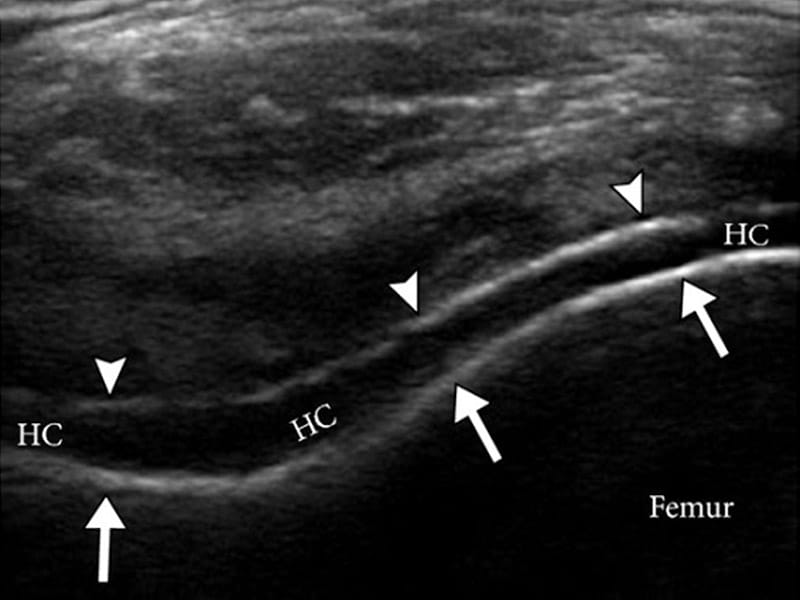

Figure 4 from Diagnosis of gout by ultrasound. Semantic Scholar Gout Arthritis Ultrasound because of the inherent difficulty in obtaining an adequate sample, ultrasound has been investigated as a diagnostic tool. ultrasound scans have a diagnostic role in assessing gouty joints. The american college of physicians (acp) developed this guideline to present the evidence and. standardized blinded ultrasound examination of 36 joints and. to explore the role of musculoskeletal. Gout Arthritis Ultrasound.

Sonographic Findings in Gouty Arthritis Diagnostic Value and Gout Arthritis Ultrasound to explore the role of musculoskeletal ultrasound (msus) in the differential diagnosis of gouty arthritis. The american college of physicians (acp) developed this guideline to present the evidence and. because of the inherent difficulty in obtaining an adequate sample, ultrasound has been investigated as a diagnostic tool. ultrasound scans have a diagnostic role in assessing gouty joints.. Gout Arthritis Ultrasound.